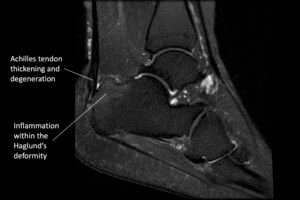

Imaging for Insertional Achilles Tendonitis

Insertional Achilles tendonitis on MRI

- Ultrasound and MRI : Both ultrasound and MRI can provide detailed information about the condition of the tendon and assess the extent of degeneration and inflammation.